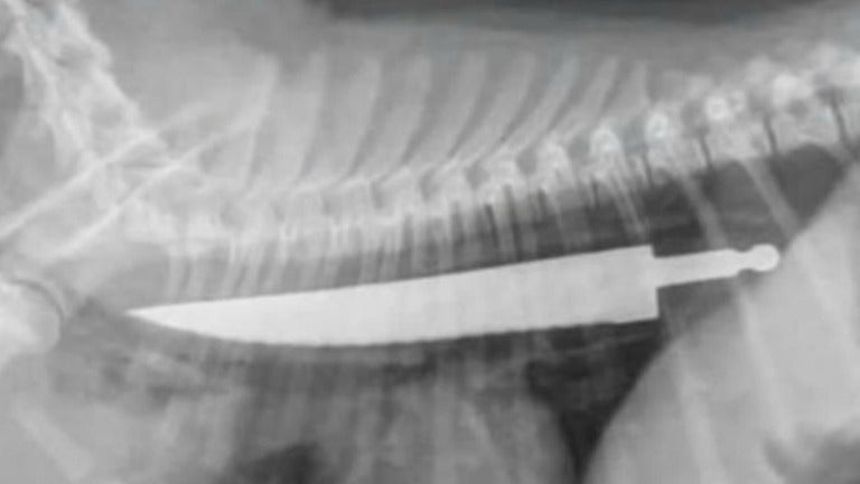

Foto de los Rayos X practicados al perro donde se ve un cuchillo en su esófago | ESPECIAL

Un hecho verdaderamente insólito sucedio en Sydney, Australia, ya que un hombre llevó a su perro al hospital veterinario donde descrubrió que su mascota se había tragado un cuchillo entero.

El cachorro de nombre Lexy se comió el artefacto sin morderlo, ni doblarlo, y fue hasta que se le hicieron estudios Rayos X que se dieron cuenta del caso.

La médico veterinario Jody Braddock aseguró que nunca había visto algo igual, esto después de extraerle el cuchillo con sumo cuidado para no cortar por dentro al perro de raza Bull-terrier.

Aunque no fue de gravedad, el perro tuvo que quedarse internado por un par de días para que tuviera cuidados especiales para checar si el objeto no había causado ninguna cortadura interior.